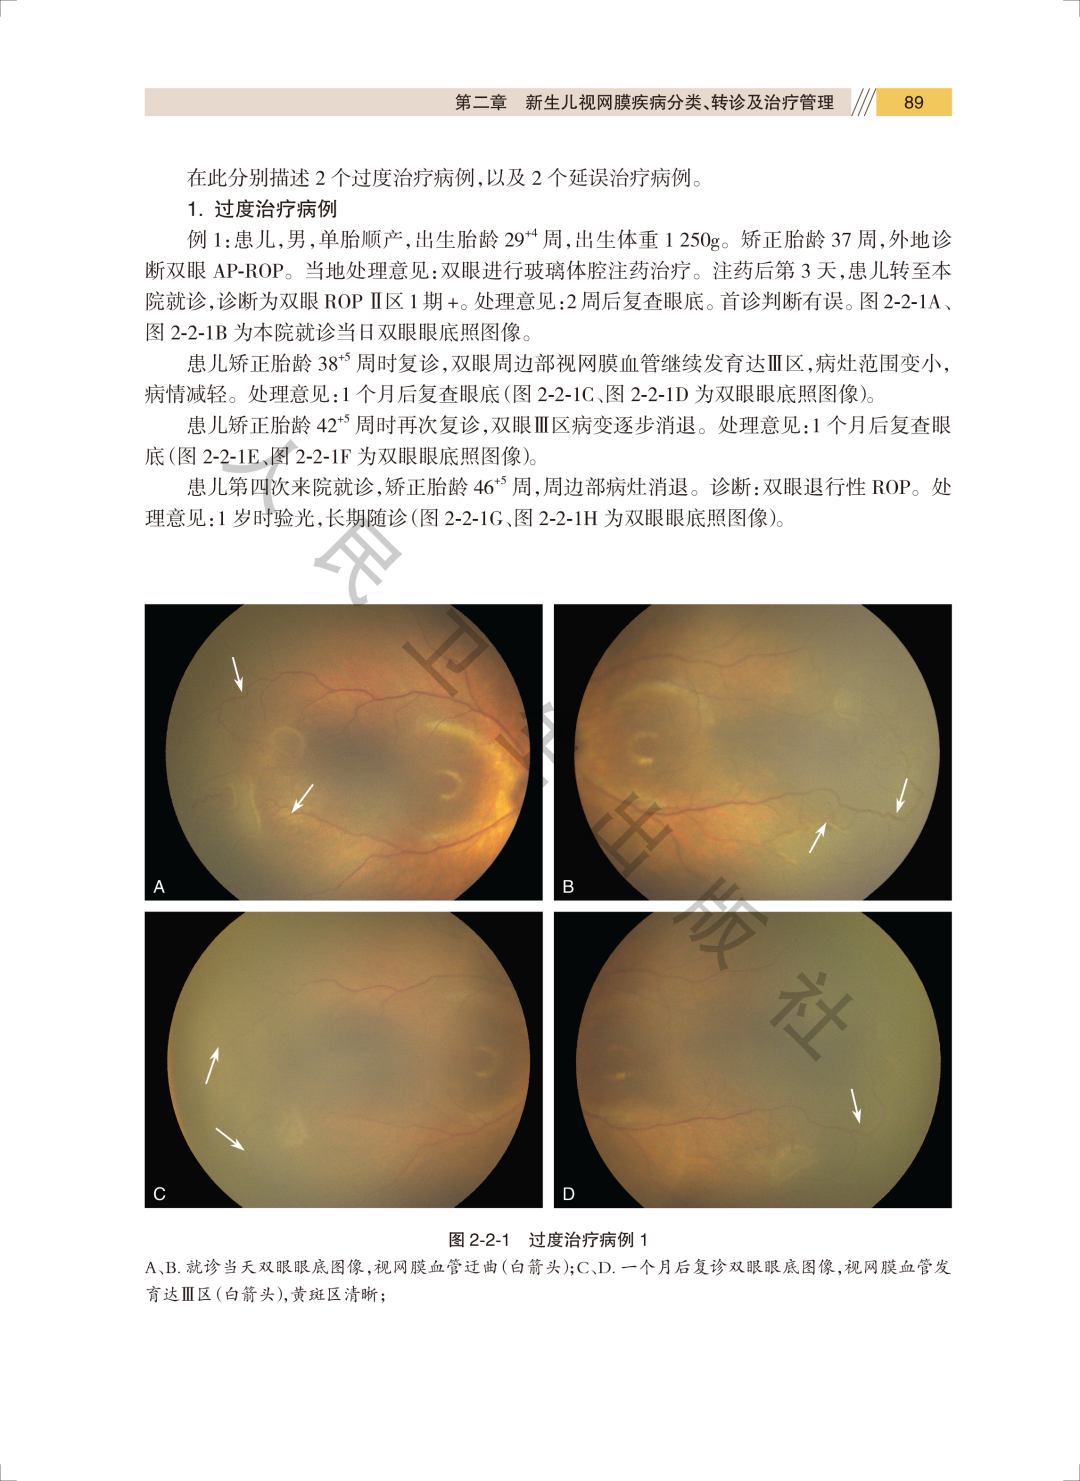

【样章试读】